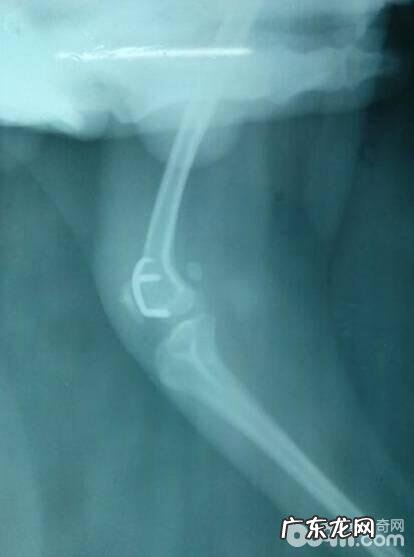

文章插图

一例小泰迪四级股骨颈里侧脱位,两岁,逆位片 。显著观查到股骨颈里侧脱位 。